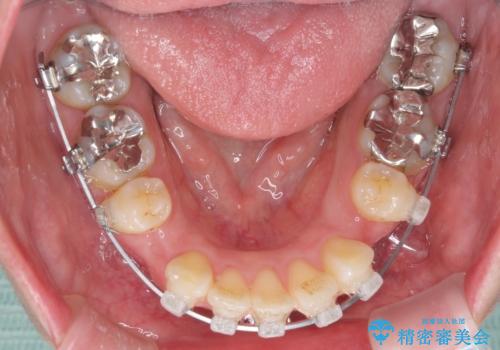

- クリアブラケット

- 2年2ヶ月

上下左右の歯を1本ずつ、合計4本抜歯して、ワイヤーにて矯正することとなりました。

もともと下の前歯の永久歯が1本欠損しており、抜歯部位の選択を考慮しなければならない症例でした。シミュレーションを事前に行い、下顎の抜歯部位を決定しました。